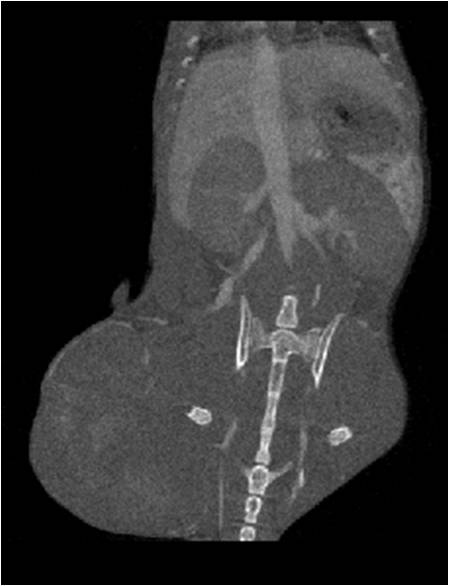

腫瘤血管生成

肺轉(zhuǎn)移

小鼠模式,22.5μm像素

正常

8天 14天

無(wú)造影劑注入 造影劑注入